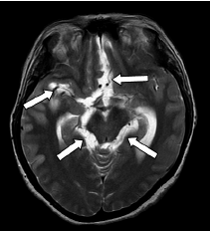

Por último, se recibió un resultado positivo de la prueba de Western blot para cisticerco en suero y en líquido cefalorraquídeo. El análisis retrospectivo de la resonancia magnética cerebral permitió concluir que se trataba de una neurocisticercosis racemosa (sic) (figura 1) y (figura 2) con vasculitis secundaria a la intensa reacción inflamatoria, probablemente generada por la muerte del parásito.

Según los hallazgos en las imágenes de resonancia magnética cerebral, los casos informados se clasificaron como neurocisticercosis extraparenquimatosa con quistes racimosos en el espacio subaracnoideo asociados a la intensa reacción inflamatoria (figura 1), (figura 4).

En los dos casos que se presentan, la neurocisticercosis racemosa (sic) se acompañó de hidrocefalia y aracnoiditis; en el primer caso, además, se detectó vasculitis de la arteria cerebral media derecha en sus porciones proximales adyacentes a las cisternas de la base y la silviana derecha, relacionada con la presencia de cisticercos (figura 1). En el segundo caso, se detectó dilatación y obstrucción del cuarto ventrículo por aracnoiditis (figura 3), hallazgo que explica la causa del vómito incoercible, debido a su estrecha relación anatómica con el área postrema (control del vómito).